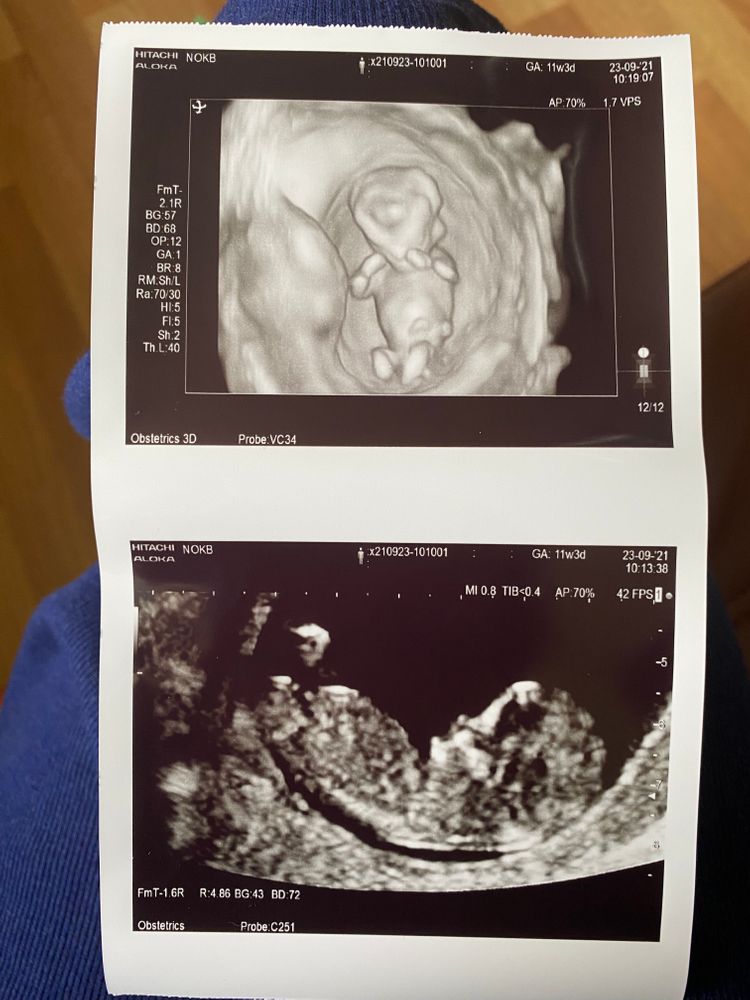

по УЗИ у нас всё в норме, все ТВП, БПР, КТР, СБ, носик, части тела и т.п. всё абсолютно хо-ро-шо. по размерам опережаем уже на целую неделю, поставили 12+2, а по месячным 11+3.

бусинка упорно закрывала лицо ручками, так мило)